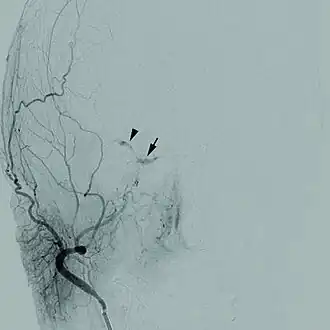

Uma angiografia cerebral de uma fístula carotídeo-cavernosa.